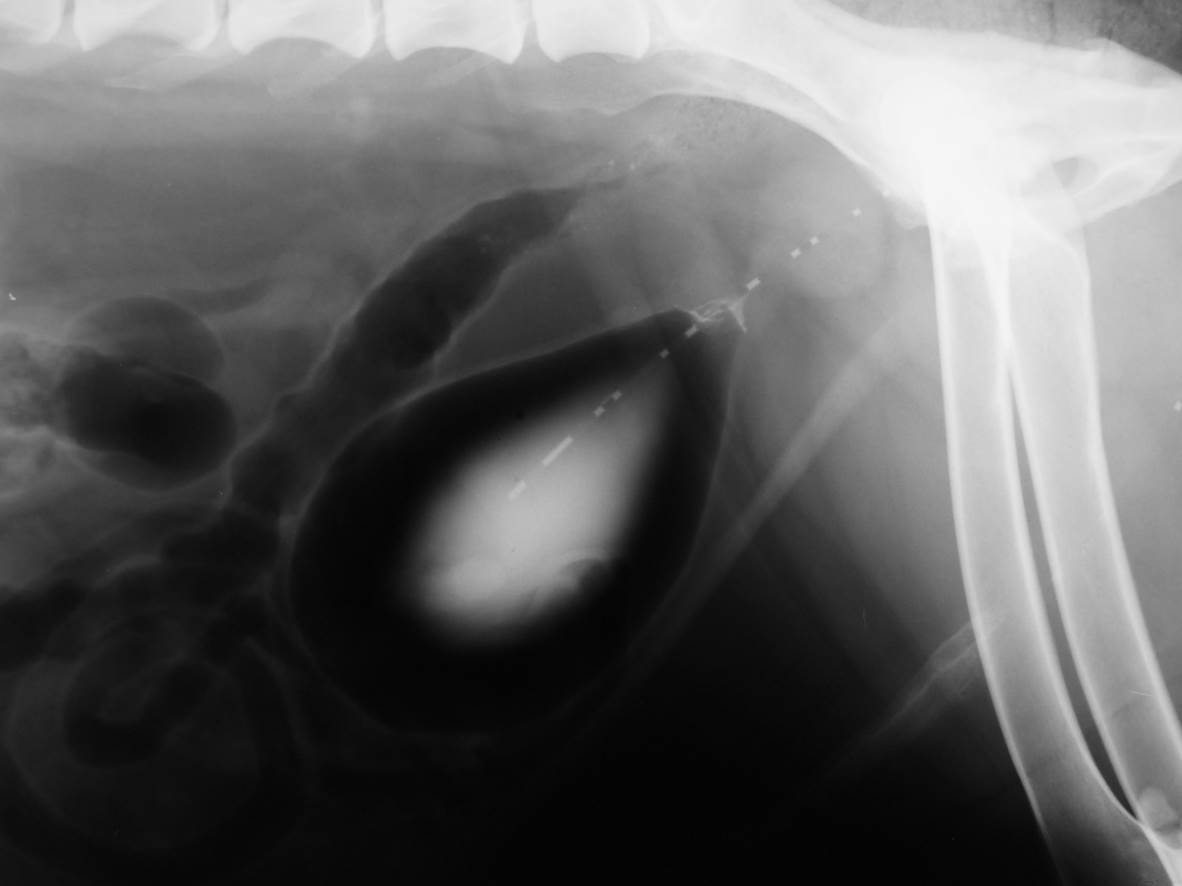

Case Joss

Discuss this case?

–catheter biopsy hopefully to confirm a benign/inflammatory lesion

–focus on identifying a UTI and managing with a prolonged course of antibiotics (?6-8 weeks minimum)

–surgical curettage of the bladder

What is Polypoid cystitis?

Polypoid cystitis is a rare disease of the urinary bladder in dogs characterized by inflammation, epithelial proliferation, and development of a polypoid mass or masses without histopathologic evidence of neoplasia.

What bacteria are/have been isolated in polypoid cystitis?

Proteus spp were the most common bacterial isolates (12/52 or 23.1%) identified when all urine samples obtained for culture at any time during the course study were considered. Other commonly isolated organisms included Escherichia coli , Staphylococcus spp, and Enterococcus spp. Several dogs (7/17) also had cystic calculi at some time during the course of their disease.

Where are most of the masses found in polypoid cystitis?

Most of the masses (11/14) were located cranioventrally in the bladder as opposed to transitional cell carcinoma, which has a predilection for the bladder neck or trigone area. It is unknown whether persistent or recurrent UTI predisposes to polyp formation or if polyps predispose to UTI.

What is the treatment for polypoid cystitis?

Surgery and removal of all polyps was the most efficacious treatment in dogs of this study. The question of whether or not polyps represent preneoplastic lesions remains unanswered and constitutes an area for future investigation